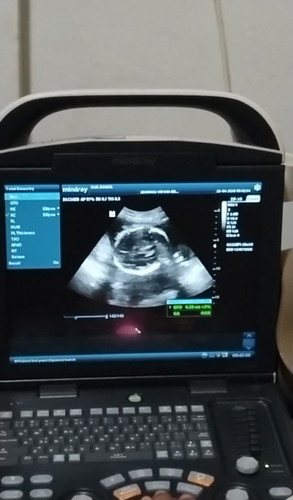

Aku bingung Bun, suami gak kerja udah hampir 2 bulan ini, aku punya anak 2, sekarang lagi hamil anak ke 3 hpl juli. Sementara keluarganya suami bener2 gak ada bantu sama sekali, selama ini kami hidup dari orang tua ku. Ya makan, jajan anak, sampai kami masih tinggal sama orang tua ku. Aku sama suami udah berusaha untuk mencari pekerjaan, tapi belum dapat. Sementara BPJS aja kami belum punya.😭😭 Gimana nanti aku mau lahiran, sedih aku kehidupan kaya gini Bun😭#Sharingdong_Bund #sharing